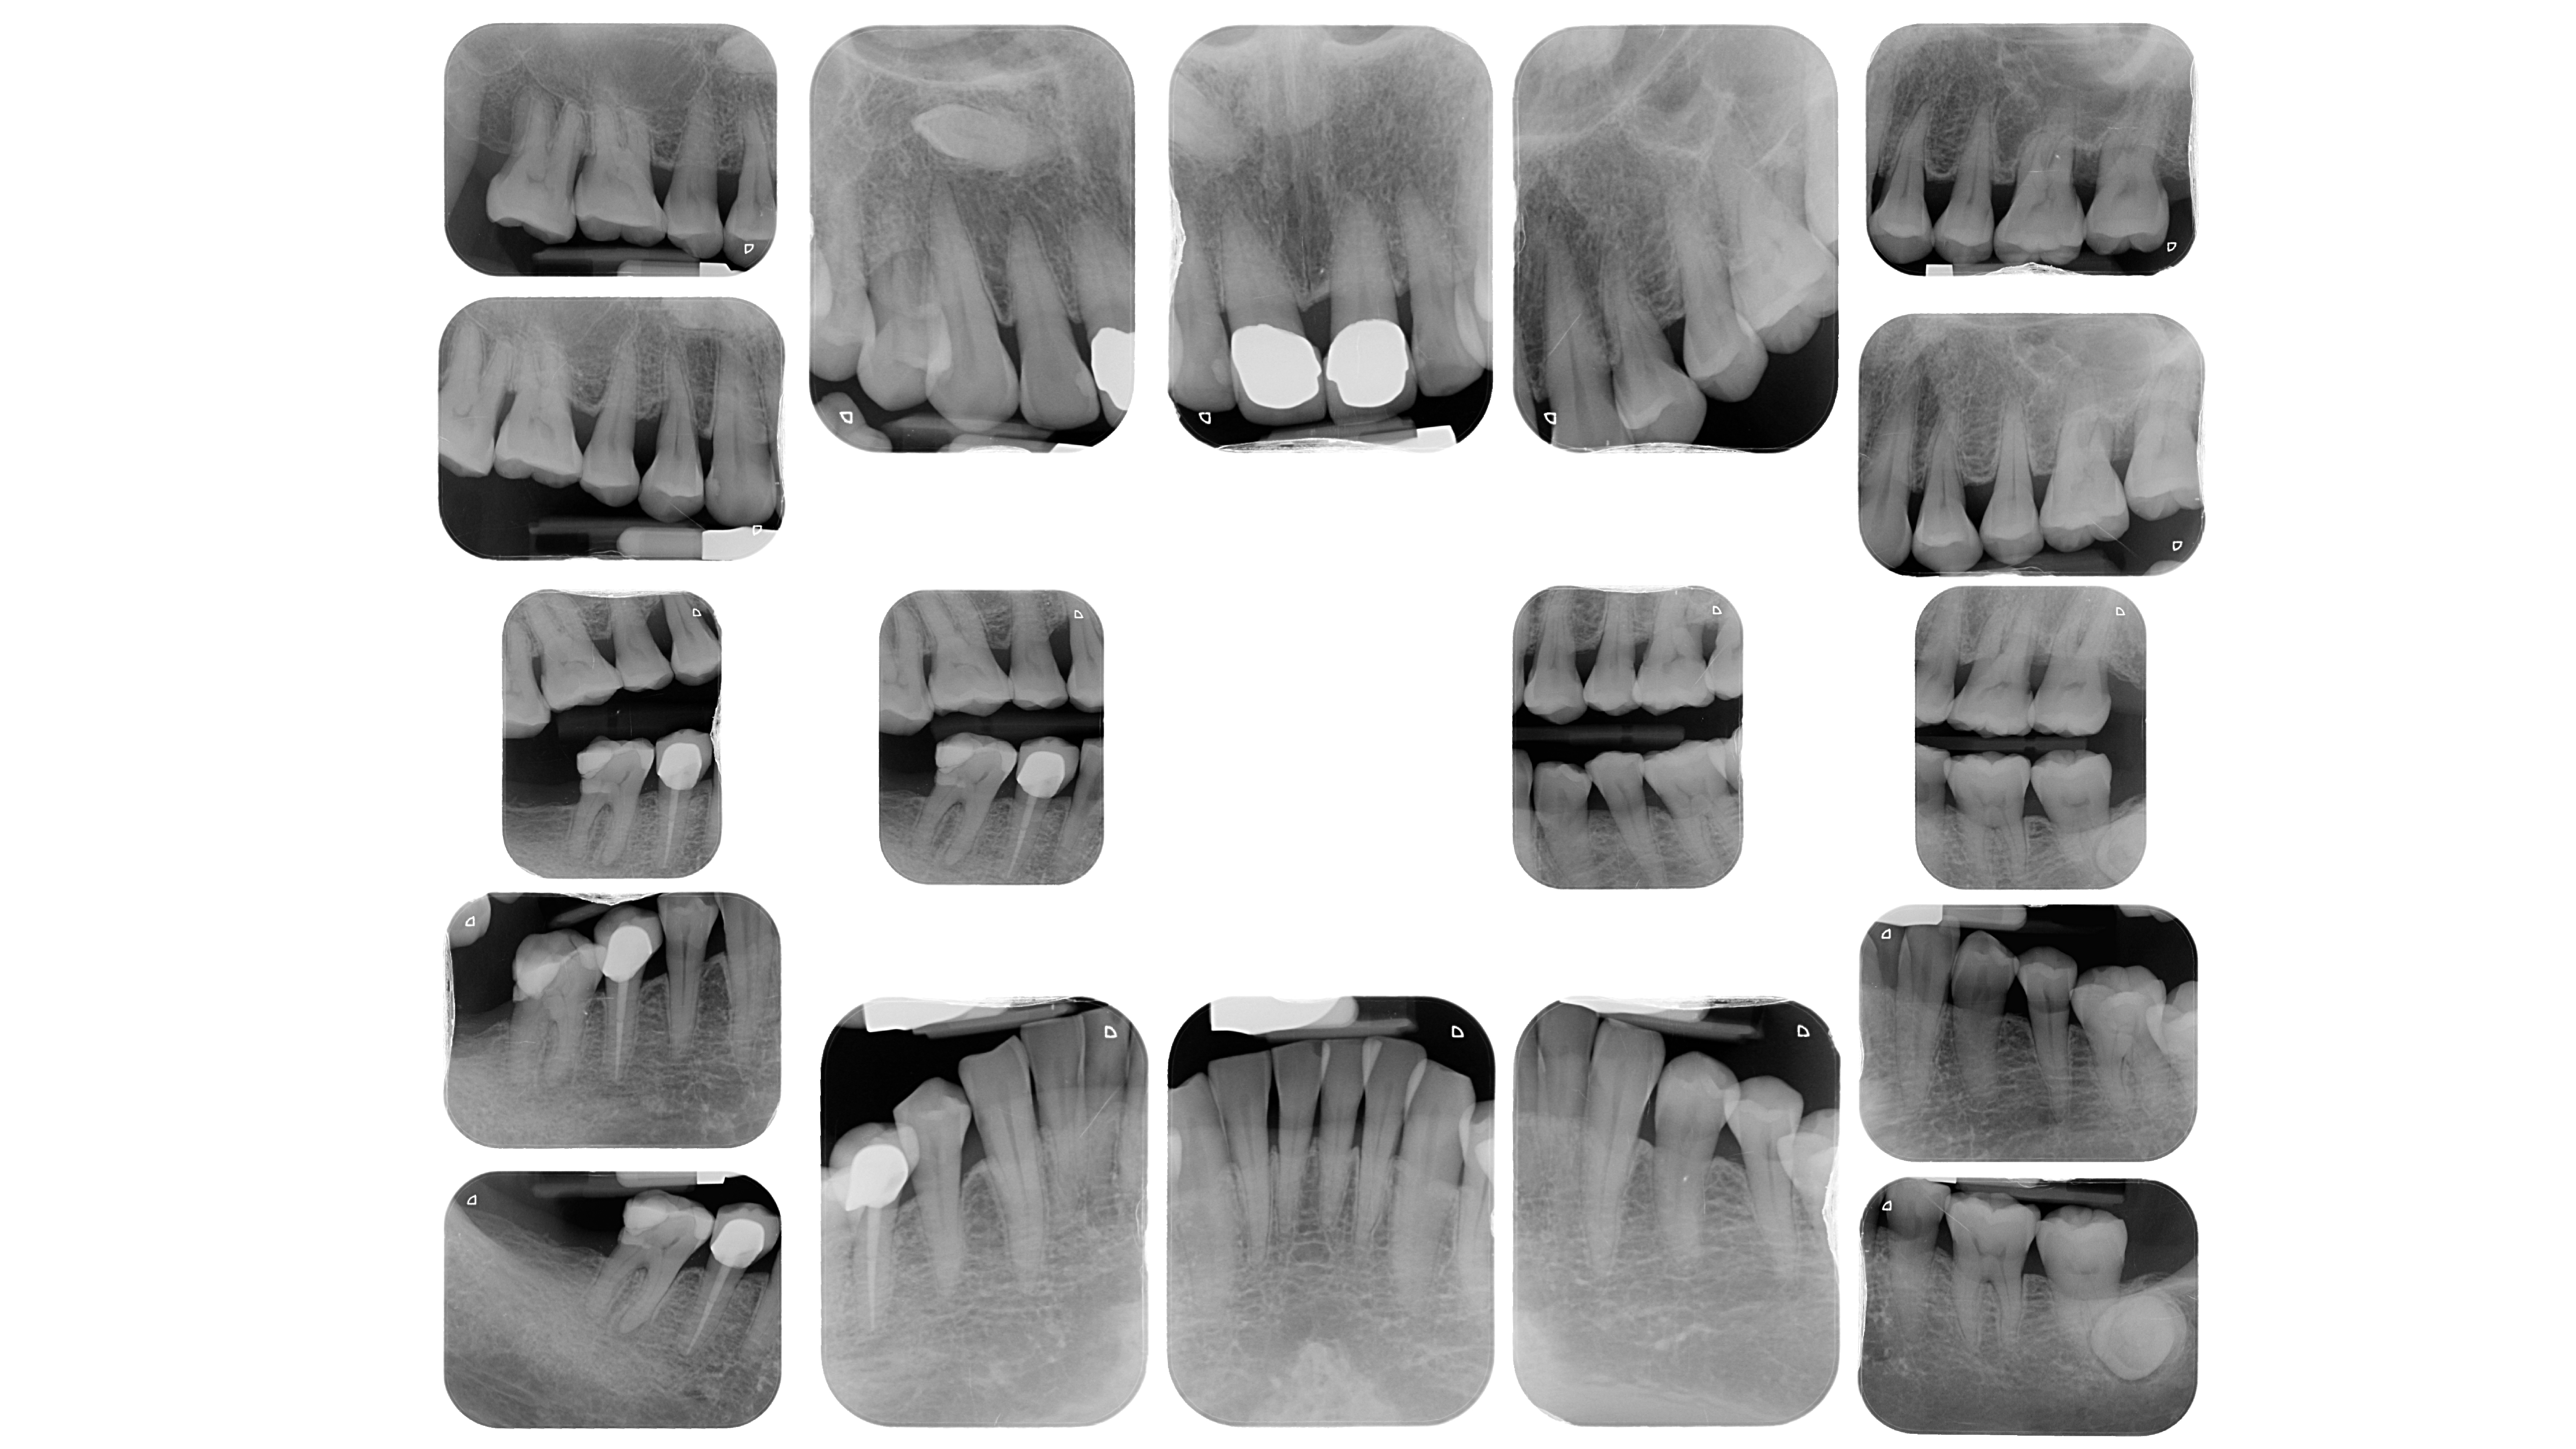

項目2:拍攝全口X片

拍攝全口細部的X光片,對於每一顆牙齒周邊的骨頭破壞程度,以及後續在牙周病的治療會有很大的幫助。